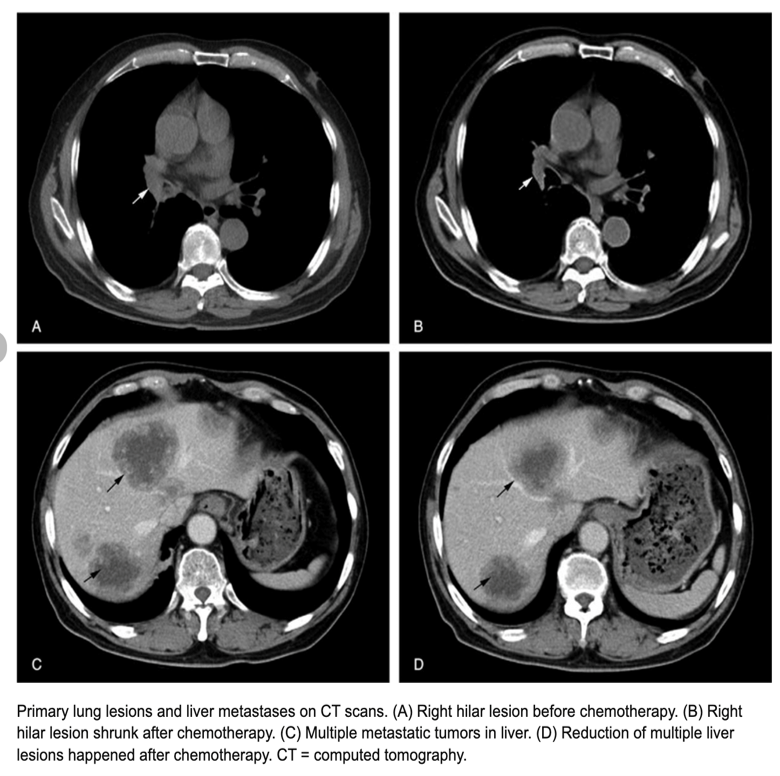

Axial CT of the abdomen showing multiple liver metastases.

Target appearance

Computed tomography (CT) scan performed in April 2016 shows three liver lesions (LLs) in arterial phase. a. The arrow indicates LL (diameter: 7 mm) with contrast enhancement suspected of metastasis at 4th segment.